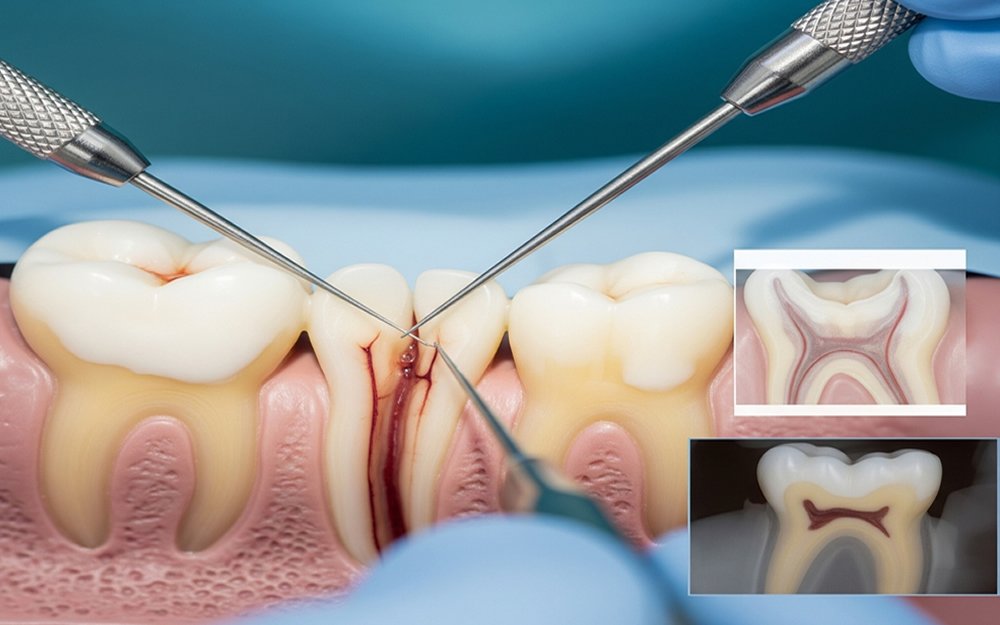

Root Canal Treatment (RCT) is a dental procedure used to save a badly damaged or infected tooth. When the inner pulp becomes infected due to decay, cracks, or injury, it can cause intense pain and swelling. RCT removes the infection, relieves pain, and restores the tooth without removing it.

Dr. Kapoor examines your tooth using advanced digital X-rays to assess infection and root structure for accurate diagnosis.

The area is fully numbed to ensure a comfortable and painless root canal treatment in Rajouri Garden.

A small opening is made and the infected pulp tissue is carefully removed from the root canals to eliminate pain.

The canals are cleaned, shaped, and disinfected to remove bacteria and prevent future infection.

The canals are filled with a biocompatible material and sealed to complete the root canal treatment safely.